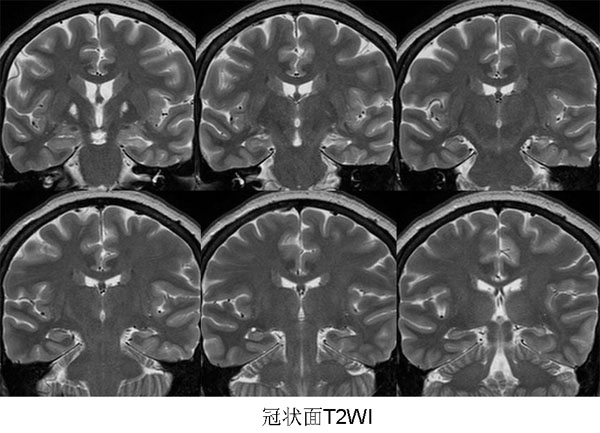

以下是引用三博在2009-9-10 12:42:00的发言:[br]病理:左侧海马硬化。[br]苍白球软化灶。[br]左侧海马信号增高,体积变小,右侧海马信号未见明显异常,